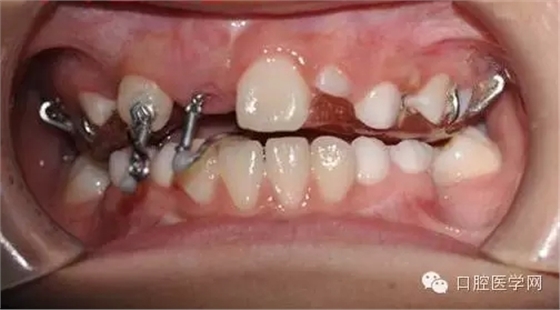

帶入口內調整吊桿方向加輕力:

(咬合調整好,加輕力激活)

每周復診:清洗,加力,適當調整吊桿方向